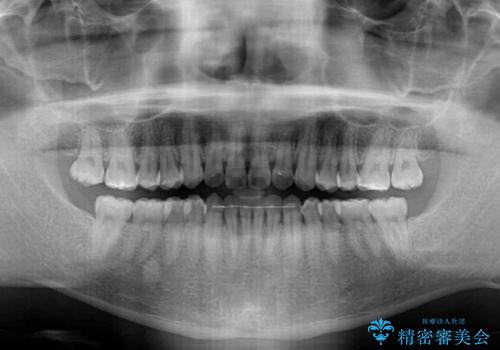

インビザラインで奥歯の咬み合わせと前歯のデコボコを改善

- 前歯のデコボコと奥歯の咬み合わせを気にして来院された患者様です。

前歯のデコボコはインビザラインで十分に対応可能と判断できましたが、咬合力が強いため、臼歯(特に右側)の交叉咬合はインビザライン単体では困難と思われました。

まずはインビザライン単体で矯正治療を開始し、交叉咬合が改善されない場合にはアンカースクリューなどの使用を検討することとしました。

インビザライン単体では右側の交叉咬合を解消することができなかったため、アンカースクリューを併用して咬合を改善させました。